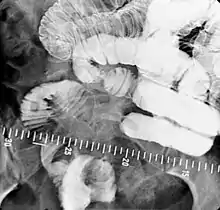

- Barium follow-through examinations are used to study the small intestine.[2]

Indications to do this procedure are: unexplained chronic abdominal pain with weight loss, unexplained diarrhea, anemia which is caused by gastrointestinal bleeding or dependent on blood transfusion where the cause cannot be explained despite OGDS or colonoscopy investigations, partial obstruction of bowel/small bowel adhesive obstruction suspected, and unexplained malabsorption of nutrients.[13] For barium follow-through examinations, a 6-hour period of fasting is observed prior to the study.[10]

Barium is administered orally, sometimes mixed with diatrizoic acid (gastrografin) to reduce transit time in the bowel. Intravenous metoclopramide is sometimes also added to the mixture to enhance gastric emptying.[17] 600 ml of 0.5% methylcellulose can be given orally, after barium meal is given, to improve the images of small bowel follow-through by reducing the time taken for barium to pass through the small intestines, and increase the transparency of the contrast-filled small bowels.[18] Other methods to reduce transit time are to add ice cold normal saline after the administration of barium saline mixture[19] or to give a dry meal.[20]

X-ray images are then taken in a supine position at intervals of 20–30 minutes. Real-time fluoroscopy is used to assess bowel motility. The radiologist may press or palpate the abdomen during images to separate intestinal loops. The total time necessary for the test depends on the speed of bowel motility or transit time and may vary between 1 and 3 hours.[17]

- Barium follow-through examinations are the most commonly used imaging technique in assessing patients with Crohn's disease, although CT and magnetic resonance imaging are widely accepted as being superior.[1] However Barium examinations remain superior in the depiction of mucosal abnormalities.[24] The features of Crohn's disease are well described by barium follow-through examinations, appearing as a typical "cobblestone pattern", but no information is obtained regarding extraluminal disease.[28] Radiographic imaging in Crohn's disease provides clinicians with objective evaluations of small bowel regions that are not accessible to standard endoscopic techniques.[29] Because of its length and complex loops, the small intestine is the most difficult part of the gastrointestinal tract to evaluate. Most endoscopic techniques are limited to the examination of proximal or distal segments, hence Barium follow-through remains in most centres the test of choice for the investigation of abdominal pain, diarrhoea and in particular diseases manifesting mucosal abnormalities such as coeliac and Crohn's disease.[26]